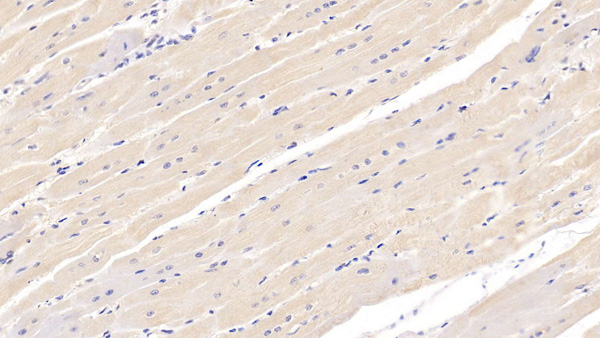

IHC (Immunohistochemistry)

(DAB staining on IHCP; Samples: Human Cardiac Muscle Tissue; Primary Ab: 20ug/ml Mouse AntiHuman NTProBNP Antibody Second Ab: 2ug/mL HRPLinked Caprine AntiMouse IgG Polyclonal Antibody (Catalog: SAA544Mu19))